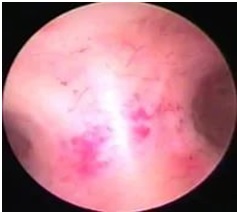

Внутриматочную перегородку по ее центру от вершины к основанию рассекали Г-образной петлей резектоскопа, последовательно, короткими движениями, монополярным током мощностью 60 – 80 Вт в чисто режущем режиме. Перегородку иссекали до формирования гладкой полости матки. Объем вводимой жидкости не превышал 6 литров; скорость подачи жидкости от 150 – 400 мл/ мин, среднее давление в полости матки – 60 – 80 мм.рт.ст. В послеоперационном периоде пациенткам в течение трех месяцев назначали гормональную контрацепцию. Метод гистероскопии расширяет диагностические возможности выявления внутриматочной патологии и выполнять оперативные манипуляции в полости матки. Окончательная диагностика внутриматочной перегородки возможна при одновременном выполнении гистеро- и лапароскопии.